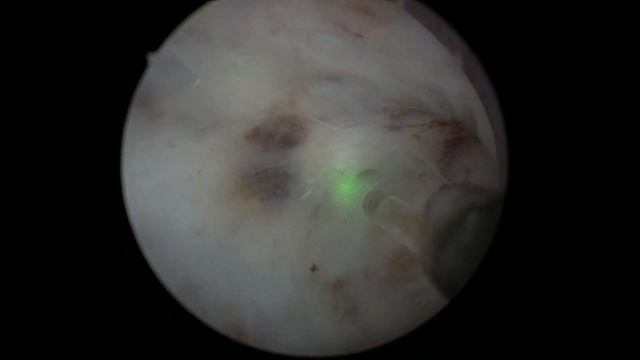

Holep уретротомия смотреть онлайн

19:00

Holep уретротомия

Brainiac Battalion Barracks 15 просмотров